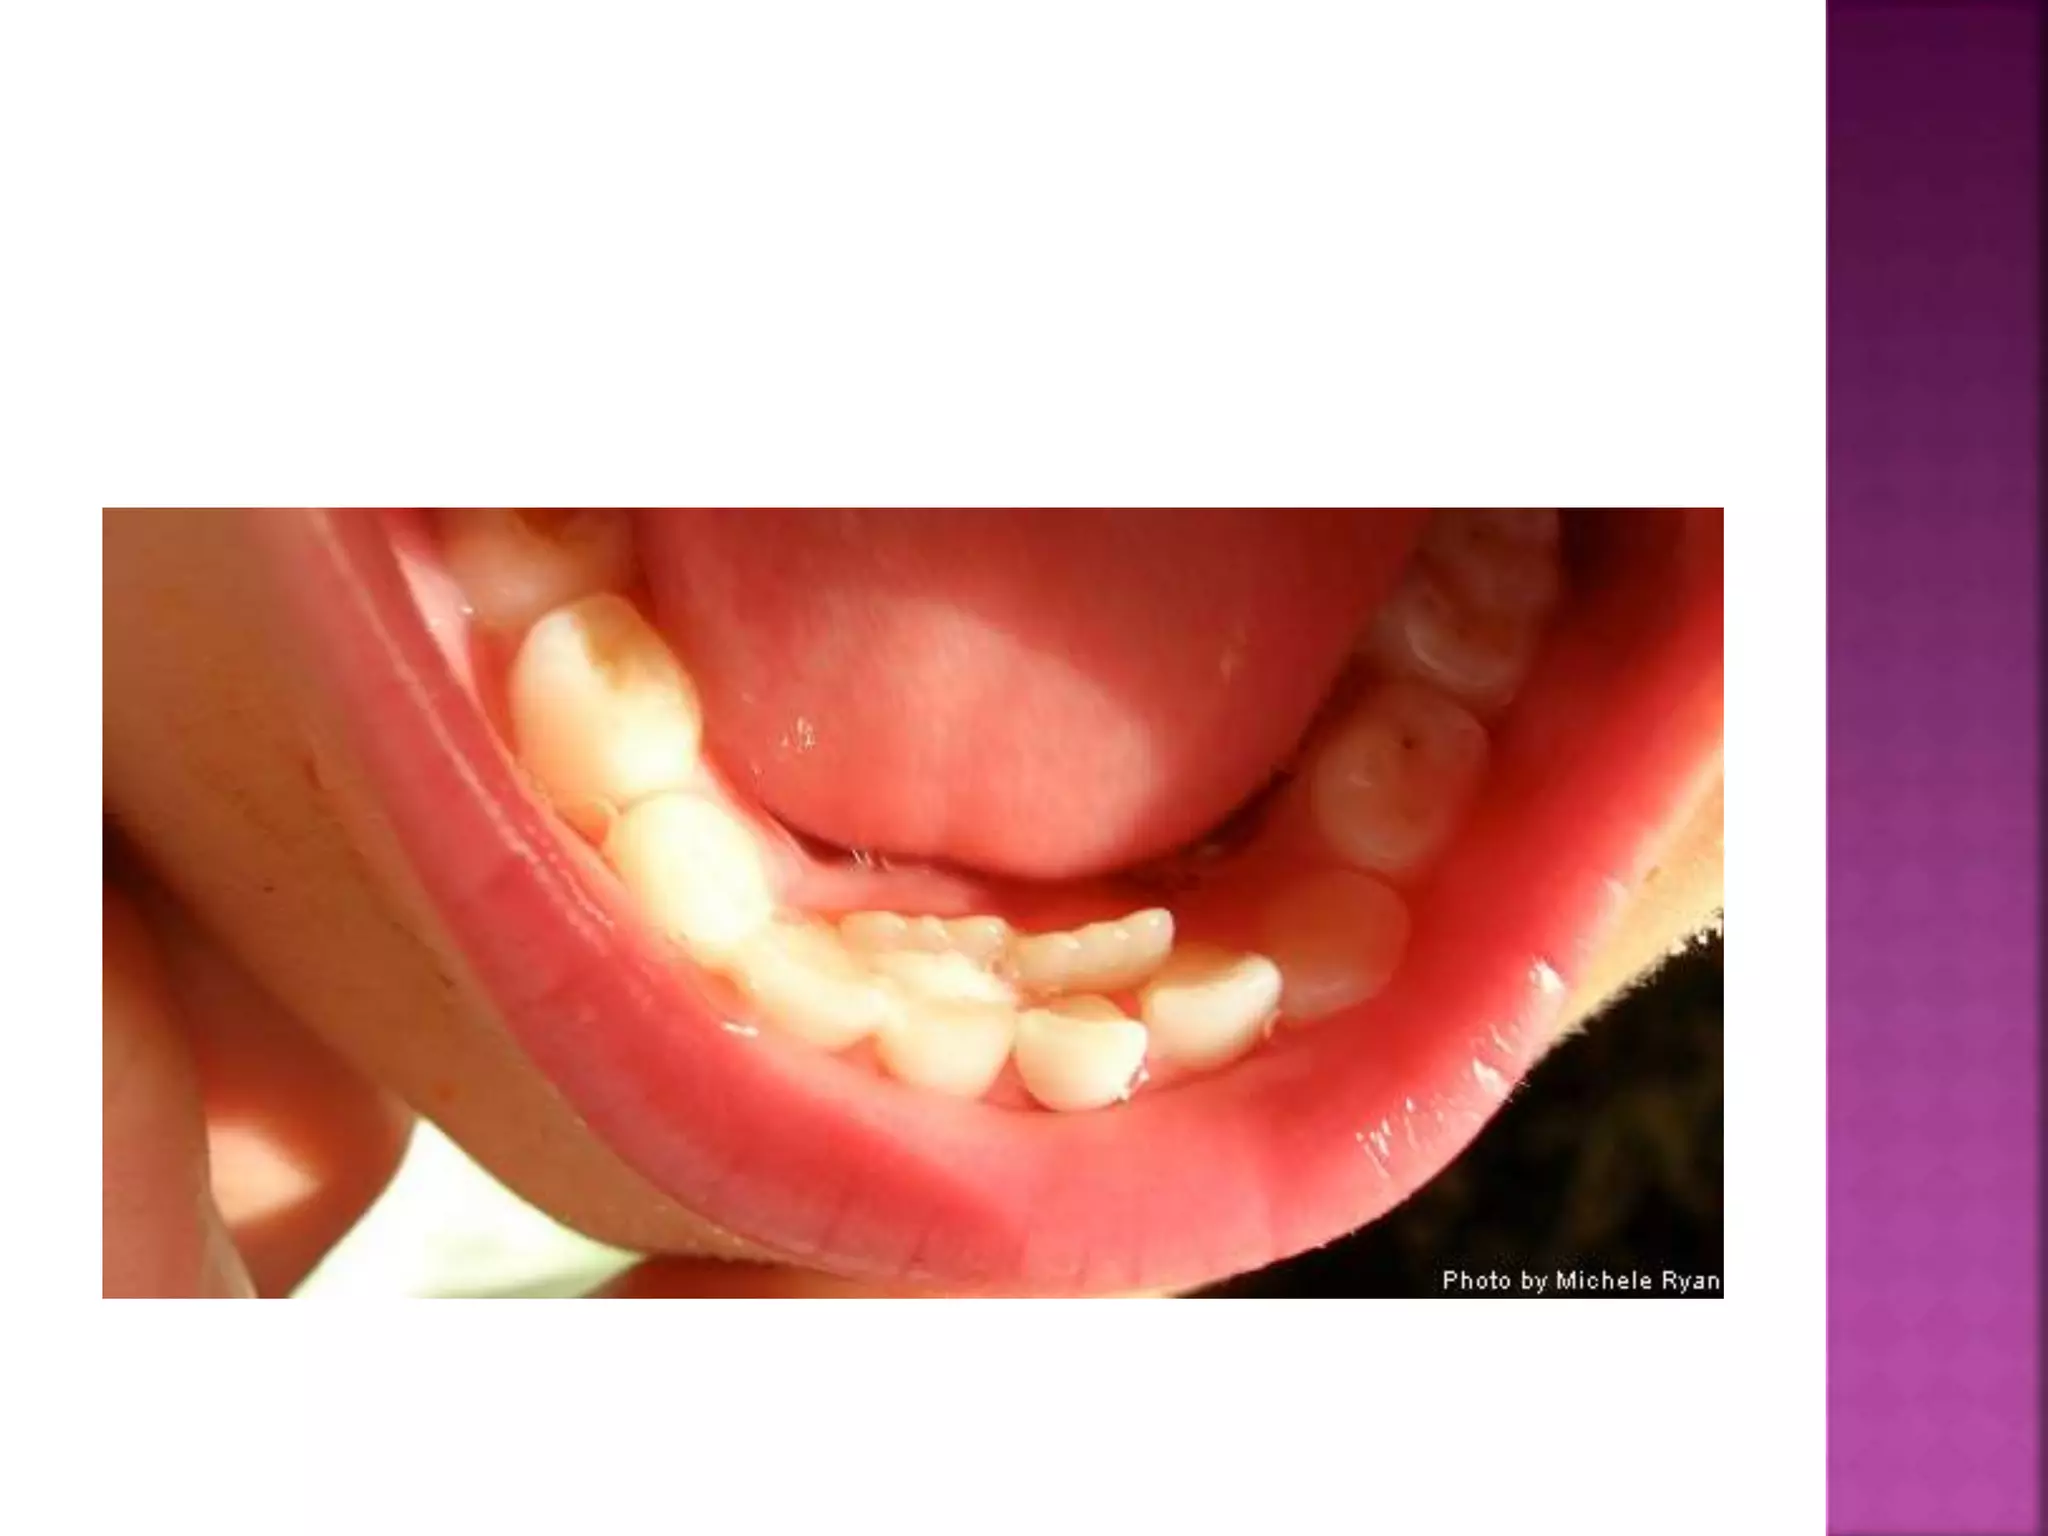

The deciduous teeth are more or less vertical in the

alveolus, so that when occlude, there is little

dislodging force ..

 When the roots of a complete permanent

dentition are examined, they show that

the degree of root curvature increase

towards the back of the mouth, i.e.,

distal inclination of the teeth axes

increases towards the end of the series

 These teeth, therefore, erupt slightly

mesially inclined, and when they come into

occlusion, they exert upon each other an

equal and opposite force.